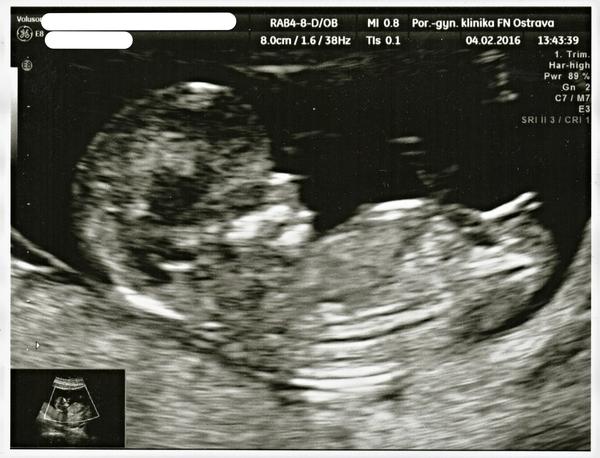

Teda když koukám na ty fotky z UZ tak musím uznat, že já měla štěstí 🙂 a prtě se hezky ukázalo 🙂 🙂 ... od začátku nám tvrdí, že to bude holčička tak budu doufat že tomu tak i bude 🙂 příští týden mě čeká velký UZ na kterém se to pokud to dobře půjde i prý potvrdí.... tak jsem zvědavá.... první fotka je z cca 10týdne ta druhá je měsíc stará.... 🙂 ale i tak než to vykoukne na svět tak člověk jistotu stejně nemá 🙂 🙂